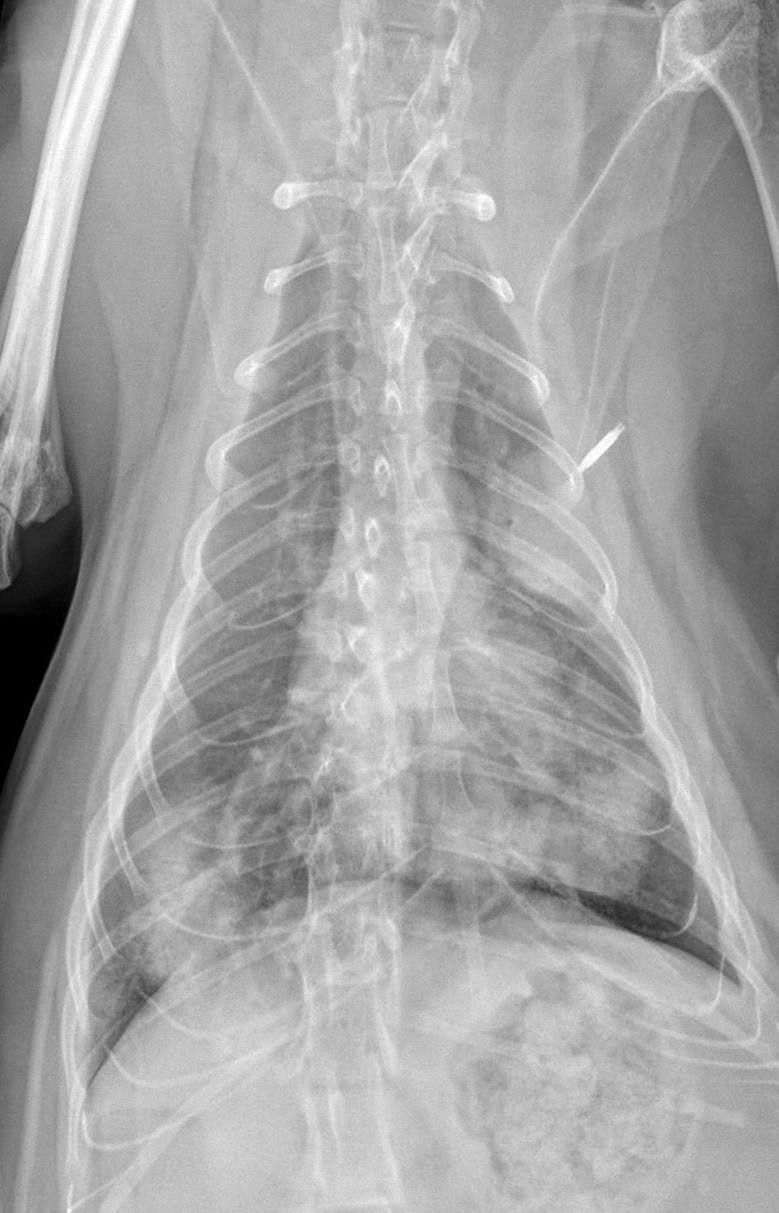

For today’s case, we have a 1.5-year-old female neutered cat with history of vomiting and coughing, with increased respiratory sounds. What are possible causes of the pulmonary pattern?

VD Thorax

There are multiple areas of ill-defined interstitial to alveolar pattern throughout the lungs. This region in the left cranial lung lobe is causing a lobar sign. The lungs overall have an interstitial appearance. The cardiovascular structures are normal, and there is no evidence of pleural effusion.

The most likely cause of the pulmonary disease is an infectious inflammatory process such as fungal pneumonia. Noninfectious inflammatory disease may also be considered.

Fine needle aspirates of the lungs and serology revealed a fungal infection (Cryptococcus). After two months of antifungal treatment, radiographs showed a marked improvement of the pulmonary pattern.